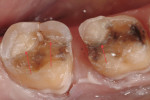

In general, aluminum-oxide pastes are safe for porcelains.20 Aluminum and aluminum oxide can both be used on stain-free surfaces. However, if ceramic restorations need to be polished to improve shine or luster, a product containing diamond particles should be chosen. Always follow the manufacturer’s recommendations for specific polishing agents to ensure proper results and success; see Case 1 (Figure 9 through Figure 13) and Case 2 (Figure 14 through Figure 20).